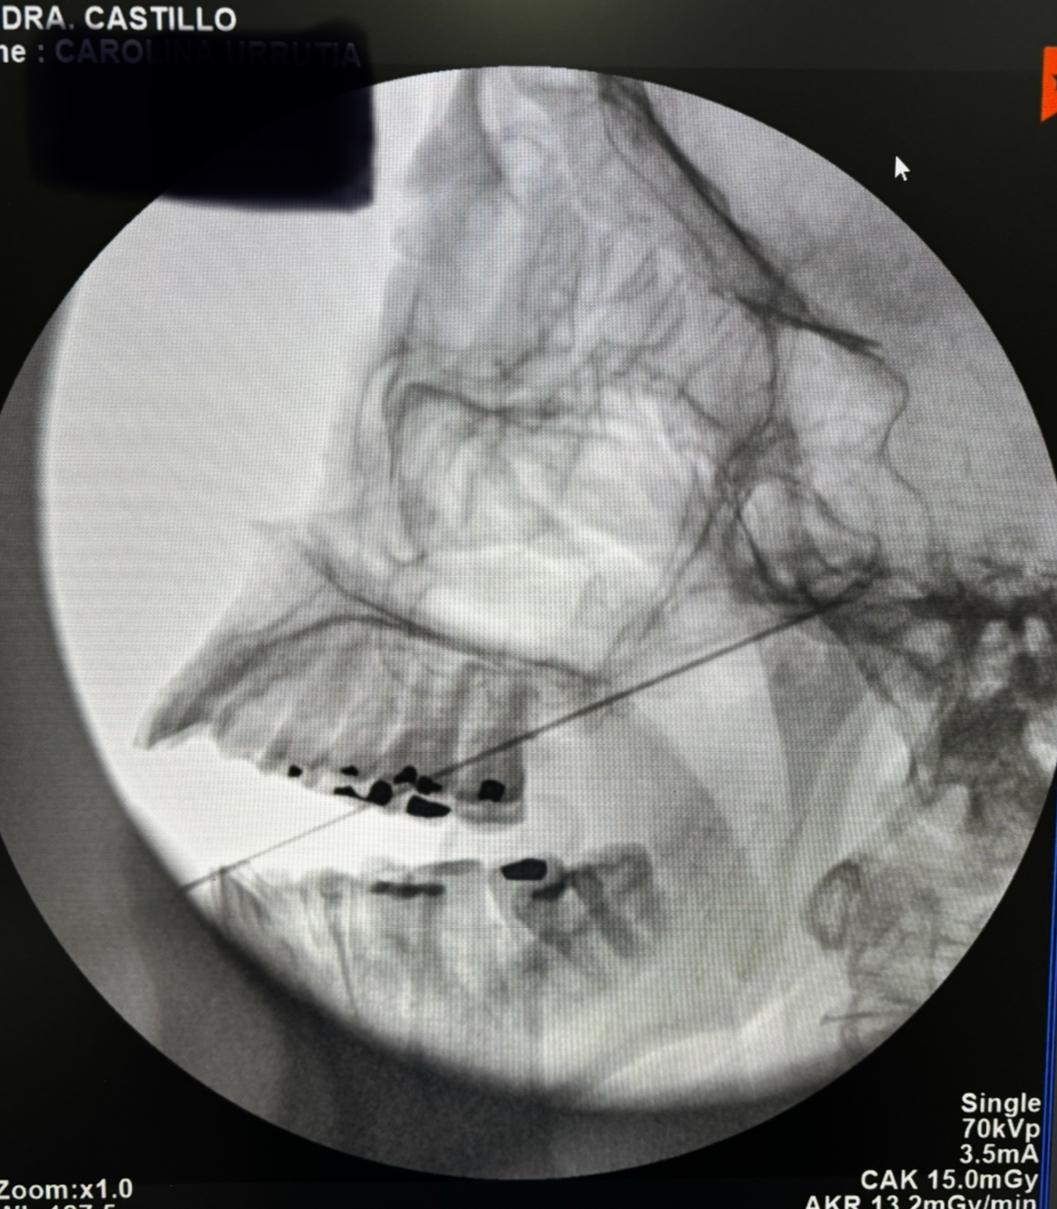

Bloqueo transforaminal de L5 bilateral por dolor radicular tipo corriente severo irradiado a ambos miembros inferiores